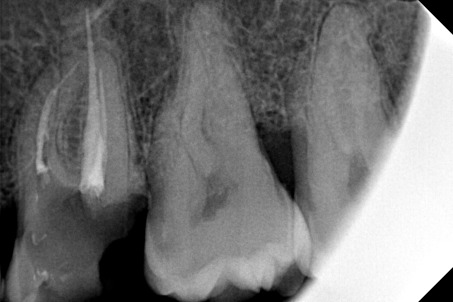

ΜΕΤΑ